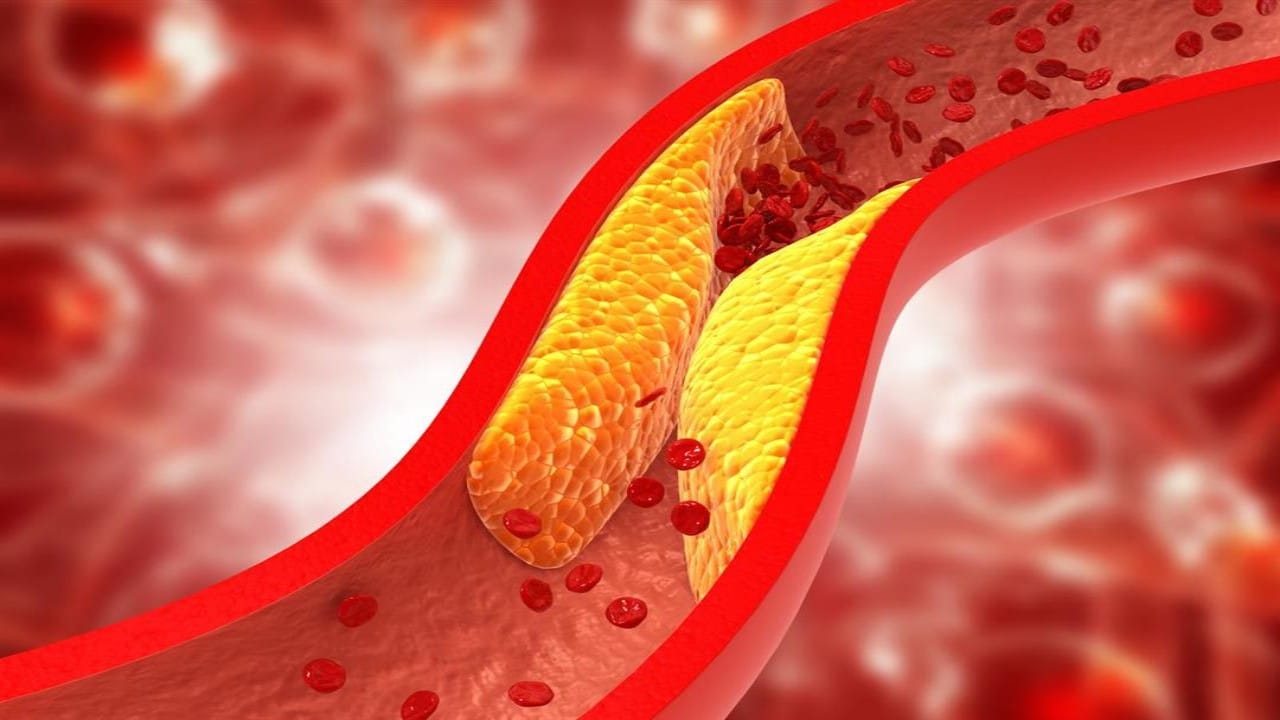

نصائح هامة للوقاية من ارتفاع نسبة الكوليسترول